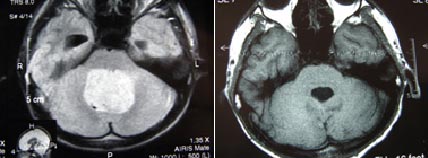

病例1:

髓母细胞瘤术前 髓母细胞瘤术后